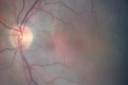

This has been a bad 3 months. Last month was the worst. When he first had cataract surgery after both were done, he was doing pretty well. He could read the paper. Then all of a sudden a fog would go past his eyes. Had ECCE OU about 6 months ago. VA OD: sc20/50 PHNI NscJ10 VA OS: sc20/63+1 PHNI NscJ10 Swelling did not respond to drops but did to a posterior subtenon kenalog injection

Pseudophakic Cystoid Macular Edema Both Eyes411 views81 year old man with vision loss about 4 months following ECCE. Did not respond to topical therapy but did fine with PST kenalog00000